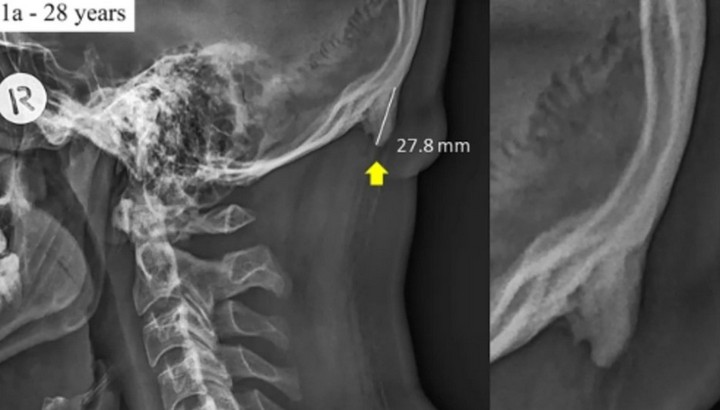

Trong nghiên cứu được đăng tải trên tạp chí giải phẫu năm 2016, Shahar và đồng tác giả đã mô tả về việc anh phát hiện ngày càng nhiều những vết lồi xương chẩm bên ngoài trong ảnh chụp X-quang của các bệnh nhân tương đối trẻ đến với phòng khám của anh. Để tìm hiểu nguyên nhân, nhóm nghiên cứu của Shahar đã tiến hành phân tích 218 mẫu chụp X-quang cột sống cổ, nơi xuất hiện các vết lồi của xương chẩm trên người có độ tuổi từ 18-30 tuổi. Mức độ nhô ra khoảng 5mm được coi là hiện tượng lồi xương chẩm ngoài và trên 10mm là lớn.

Trong số đó, họ nhận thấy có 41% người bệnh bị lồi xương chẩm và phần gai dài ít nhất 20mm. Điểm đáng chú ý là hiện tượng này xảy ra phổ biến ở nữ giới với 67% so với 20% ở nam giới. Phần xương lồi dài nhất ở nam là 35,7mm và nữ là 25,5mm.

Nghiên cứu cho biết, trường hợp enthesophyte nhô ra khỏi xương chẩm ngoài rất hiếm gặp trong các tài liệu y khoa. Một nghiên cứu vào năm 2012 dựa trên phân tích 40 hộp sọ chỉ tìm thấy một trường hợp có lớp xương lồi ra khoảng 9mm.